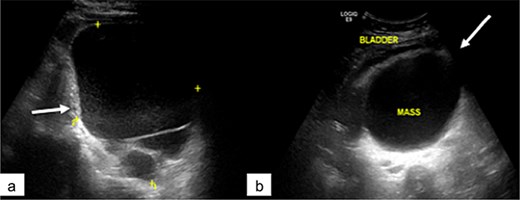

Abdominopelvic ultrasound revealed a large cystic mass occupying the abdominopelvic region and extending posteriorly, displacing the bladder anteriorly (Fig. 1). The lesion was multilocular and showed no significant vascularization on Doppler imaging.

Pelvic ultrasound showing a large multilocular pelvic mass (arrow), displacing the bladder anteriorly.